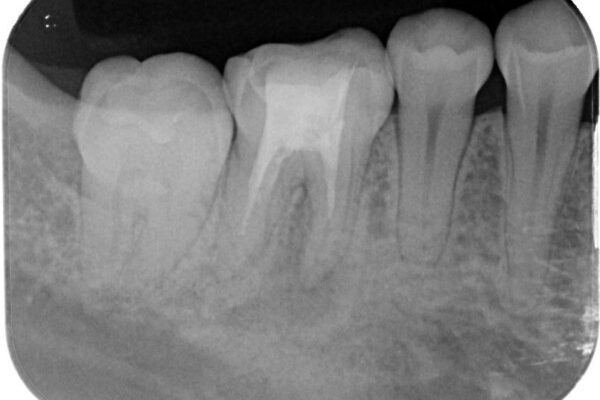

「以前に根管治療をした歯が、噛むと違和感がある」とのことでご来院された患者様の症例です。 患者様は、数年前に他院で根管治療を受けたとのことでしたが、被せもの(クラウン)は装着されていない状態でした。 噛んだときの違和感が慢性的にあり、食事中も気になるとのことで当院にご相談いただきました。 レントゲン検査では、根の先端に透過像(根尖病変の可能性)が見られ、過去の治療ではラバーダム防湿が使用されていなかったそうです。

• ラバーダム使用で再感染リスクを抑えた再根管治療+精密な補綴による長期安定を実現 治療前画像